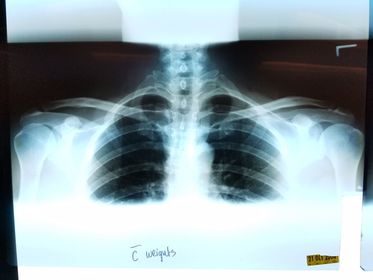

AP AC and SC Joints weight bearing and non weight bearing 72 SID 65-80 kVp 14x17 IR crosswise CR @ manubrium expose during suspended respiration *take first exposure without weights *8-10lb weights should be attached to wrists so the arms and clavicles will be relaxed for the 2nd projection

Bilateral AC Joints w/ weights